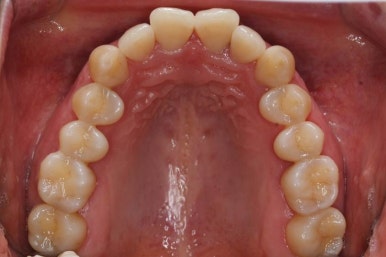

부산설측교정 키다리아저씨치과에서 부분교정을 마무리 하였습니다.

장치를 모두 제거하고 유지철사를 안쪽으로 부착하고 치료를 종료하였습니다.

전후사진을 비교해 보겠습니다.

삐뚤었던 부위들은 가지런하게 정리가 되었습니다.